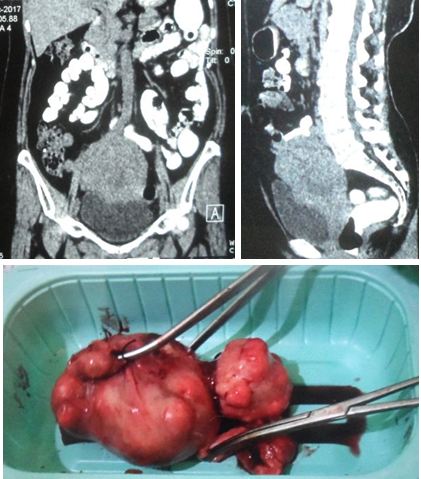

Ono underwent an operation to remove his gallbladder. A pathology report indicated a perforated gallbladder with malignant glands. It was a moderately differentiated adenocarcinoma.

CT scan on 27 September 2018 indicated the following:

- metastatic liver nodules.

- metastatic paraortic lymph nodes.

- right upper lobe lung mass (2.3 x 3 cm), likely tumour, metastasis.

- small left lower lobe nodule, likely metastasis.

- right hilar and mediastinal lymph nodes.

Biopsy report dated 29 September 2018 confirmed:

- right upper lung lobe mass — moderately differentiated adenocarcinoma.

- subcarinal lymph node — no malignancy. Another report C2354-18 on the same date, subcarinal lymph node aspirate: few atypical cells that are suspicious for carcinoma.